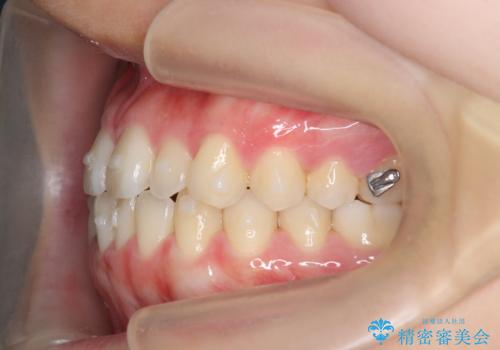

マウスピース矯正で前歯のガタつきを改善

- 上下の前歯のガタつきの改善を求めて、矯正治療を希望され来院されました。

矯正検査の結果、マウスピース矯正システム インビザラインの適応であることからワイヤーを用いず矯正治療を進めることとしました。

1日20時間以上の使用時間をきっちりと守っていただけたため、良好な治療結果、歯並びを手に入れることができました。